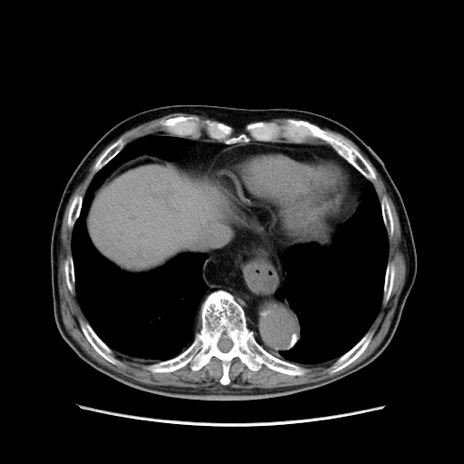

症例24(横断像)

【症例】80歳代男性

【主訴】左側腹部痛、嘔吐

【現病歴】本日早朝より左腹部に痛みあり。昼頃嘔吐認めたため、救急要請。

【既往歴】直腸癌(Mile手術)、胆摘

【身体所見】意識清明、BT 35.9℃、BP 221/93mmHg、SpO2 97%(RA) 、腹部:左ストーマ周囲に限局性の腹部膨隆あり。 膨隆部自発痛・圧痛あり・軟。

【データ】WBC 7700、CRP 0.09